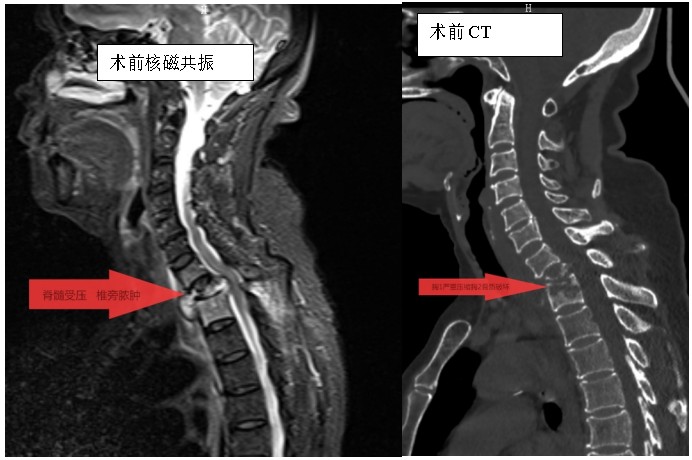

家住耒陽的70歲的李奶奶,因“頸胸背部疼痛不適伴雙上肢麻木6個月”,來到衡陽市中心醫(yī)院脊柱外科住院,住院當(dāng)天,患者頸胸椎核磁共振顯示:胸1、2椎體骨質(zhì)破壞,伴胸1、2椎旁軟組織腫脹、同層面椎管變窄,因脊髓受壓而導(dǎo)致頸胸背部疼痛。在錢軍博士帶領(lǐng)下,醫(yī)療團(tuán)隊(duì)詳細(xì)予以完善相關(guān)檢查后,研究患者的臨床資料,考慮脊柱結(jié)核并椎旁膿腫的可能性大,由于患者胸1椎體病理性骨折并椎管狹窄,遂囑患者嚴(yán)格臥床休息,術(shù)前給予標(biāo)準(zhǔn)四聯(lián)抗結(jié)核藥物治療2周,以控制活動性結(jié)核感染,降低術(shù)中播散風(fēng)險,并嚴(yán)密監(jiān)測肝腎功能及血常規(guī)情況。